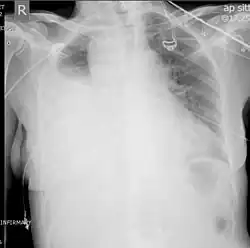

Ultrasonography may be used to detect hemothorax and other pleural effusions. This technique is of particular use in the critical care and trauma settings as it provides rapid, reliable results at the bedside.[23] Ultrasound is more sensitive than chest x-ray in detecting hemothorax.[25] Ultrasound can cause issues in people who are morbidly obese or have subcutaneous emphysema. When CT is unavailable in the current setting or the person cannot be moved to the scan, ultrasound is used.[3]

Ultrasound scan of the chest showing a left-sided hemothorax -